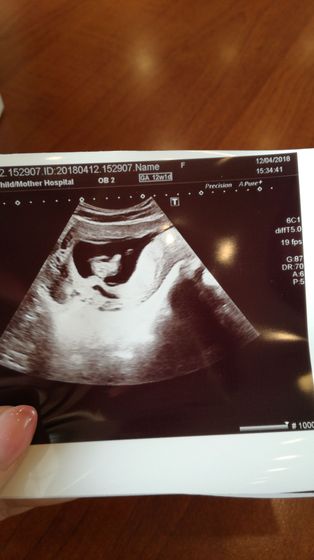

Вчера ходила на скрининг, доктор увидела отслойку, сказала небольшая, а у меня самолет в отпуск на родину через неделю, я начала беспокоиться, спрашивать, говорит ничего страшного, пить дюфастон и ставить свечи папавирин. Вроде лететь всего час, это конечно не много, но потом добираться на машине ещё часов 6 до дома, что-то я переживаю, стоит ли вообще ехать ? И ещё один такой немаловажный момент, посмотрела она меня буквально за 5 минут, сказала всё в двух словах, начинаю сомневаться, думаю может лучше сходить платно сделать? Вдруг она ошиблась? ((((Опять нервничаю, ничего поделать не могу с собой ?

У вас есть какие то выделения(коричневые, кровяные)малейшая отслойка без каких либо выделений не проходит, сходите в платное УЗИ